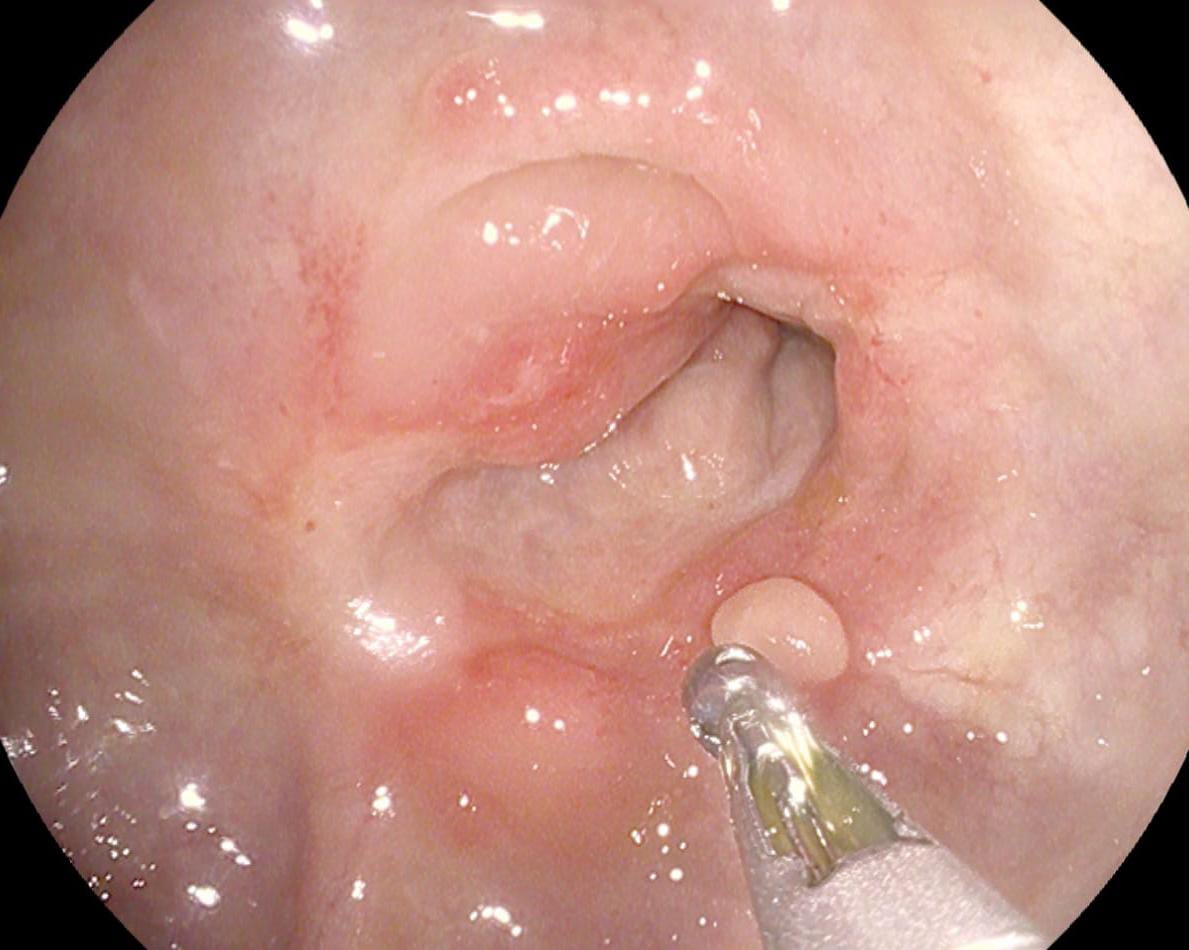

استقبل مستشفى أبو كبير المركزي حالة ثالثة لرجل مُسن يبلغ من العمر 69 عامًا بدون أسنان، أصيب بانسداد مجرى الطعام؛ نتيجة ابتلاع ليمونة كبيرة الحجم دون مضغ، حيث علقت تحت صمام المرئ السفلي، بمكان جراحة سابقة لاستئصال ورم بالمرئ.

تمكن الفريق الطبي بقسم المناظير من تفتيت الليمونة وإزاحتها لتجويف المعدة، وتم خروج الحالة بصحة جيدة.